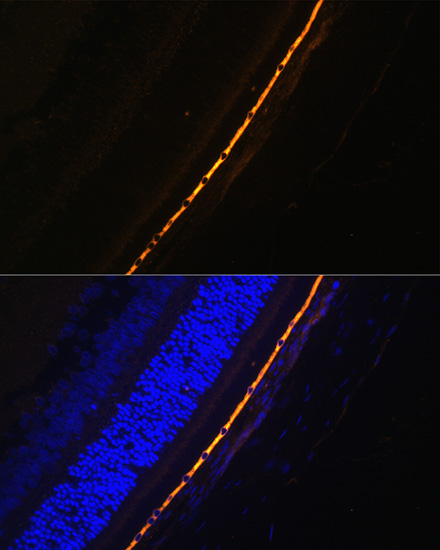

BackgroundThis gene encodes a protein which is located in the retinal pigment epithelium and is involved in the production of 11-cis retinal and in visual pigment regeneration. There are two forms of this protein, a soluble form called sRPE65, and a palmitoylated, membrane-bound form known as mRPE65. mRPE65 serves as the palmitoyl donor for lecithin retinol acyl transferase (LRAT), the enzyme that catalyzes the vitamin A to all trans retinol step of the chromophore regeneration process. Both mRPE65 and sRPE65 also serve as regulatory proteins, with the ratio and concentrations of these molecules playing a role in the inhibition of 11-cis retinal synthesis. Mutations in this gene have been associated with Leber congenital amaurosis type 2 (LCA2) and retinitis pigmentosa.

DescriptionRPE65 Polyclonal Antibody. Unconjugated. Raised in: Rabbit.

ApplicationWB, IF; Recommended dilution: WB: 1:500-1:2000, IF:1:50-1:200